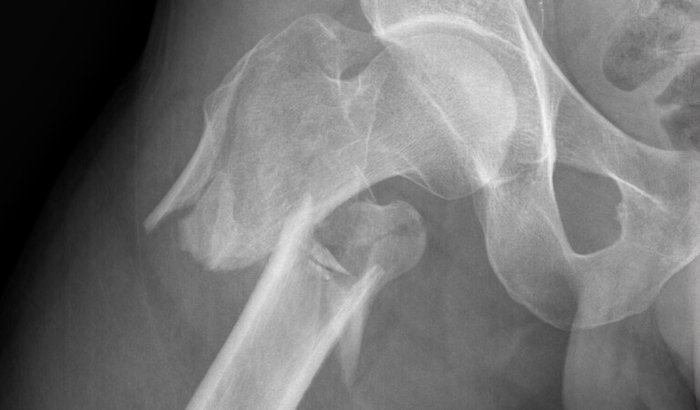

Recentemente sofri um acidente de moto que resultou em uma fratura grave no colo do fêmur – uma lesão que mudou completamente a minha rotina. Precisei passar por uma cirurgia de urgência e agora estou enfrentando um longo processo de recuperação, fisioterapia e reabilitação.